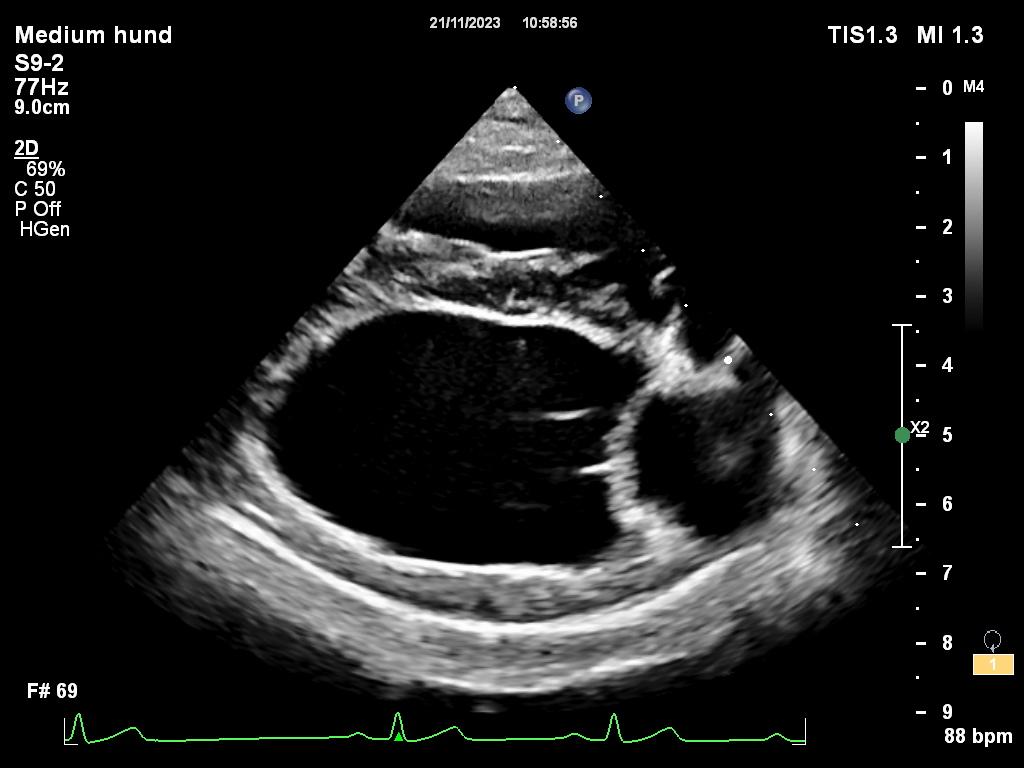

For å stille diagnose samt gradere sykdom utfører en kardiolog, en dyrlege som har spesialisert seg på hjertesykdommer, en ultralydundersøkelse av hjertet til hunden. Ved mistanke om hjertesvikt tar vi i tillegg røntgenbilder av brysthulen eller ultralyd av lungene for å se om det er væskeansamling i lungene. Er det mistanke om rytmeforstyrrelser, eller hunden kollapser, er det aktuelt med EKG undersøkelse.